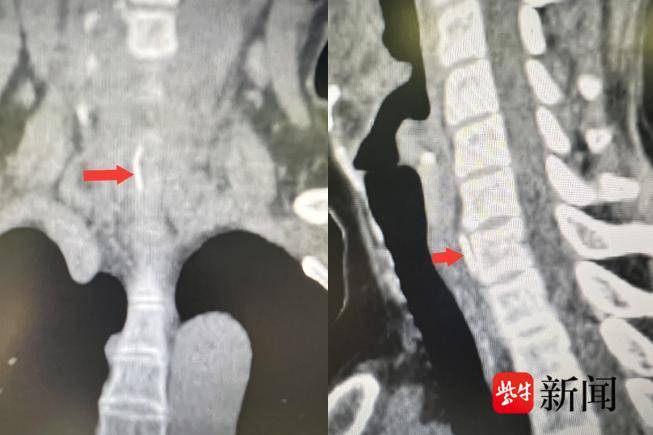

庞奶奶进一步完善了CT检查,发现食道后壁存在有异物的可能性。中大医院耳鼻咽喉头颈外科黄志纯主任医师仔细研究CT图像,并联系放射科共同阅片分析,判断异物已经穿透了食管,且位于颈椎前缘。

经过紧急手术,异物成功被取出。令人意外的是,这枚异物并非是鱼刺,而是一枚针。事后庞奶奶回忆,自己在家中加工美容纳米针。在饭桌上就着汤吃面包时,一块面包掉到了饭桌上,很可能就是在那个时候,面包粘上了一根美容针,在她吃面包时不慎将针误吞了下去。